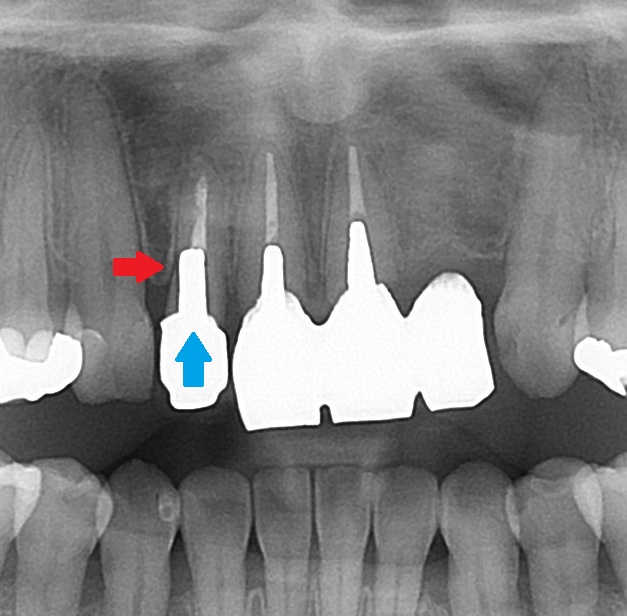

ジルコニアで治療するも、フロスが引っかかる。原因は?歯の治療を自費で受ける前の注意点。

• Before